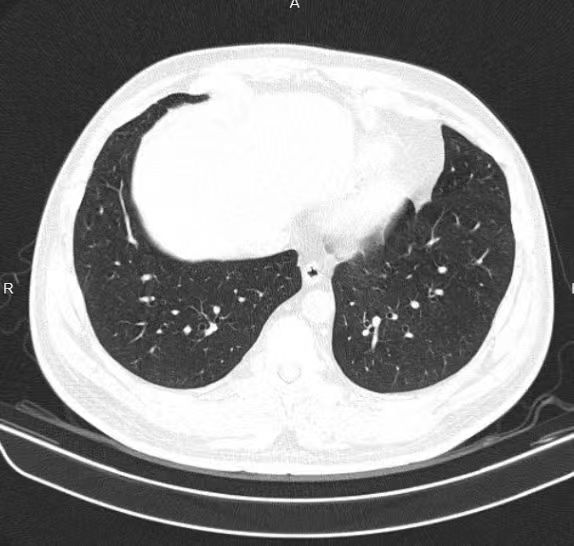

患者陳某,男,71歲,因“反復(fù)咳嗽3月” 被外院確診為“肺惡性腫瘤”,曾先后進行4次化療及30次放療,后因身體無法耐受而放棄,接受純中藥治療。此后患者納差、咳嗽癥狀持續(xù)性發(fā)作,于上海、溫嶺等地多次服中藥治療,癥狀改善不明顯。

后經(jīng)朋友介紹至我院行中醫(yī)藥治療。初服藥時咳嗽癥狀較為頑固,僅表現(xiàn)食欲改善,后經(jīng)反復(fù)調(diào)整用藥,咳嗽癥狀逐漸減輕。堅持服藥5月后患者復(fù)查CT腫塊較前縮小。